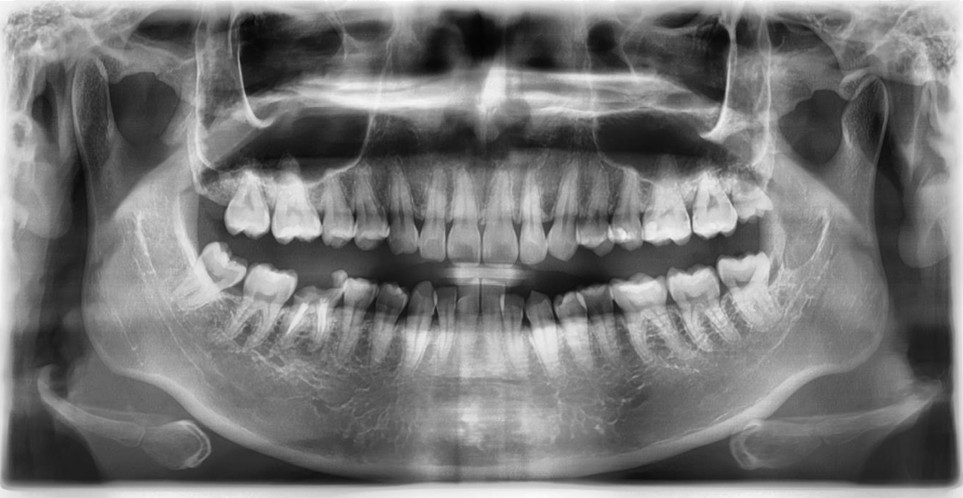

術前評估口腔狀況

右下第一大臼齒斷裂

治療計畫

右下第一大臼齒拔除, 將右下智齒移植到缺牙區域